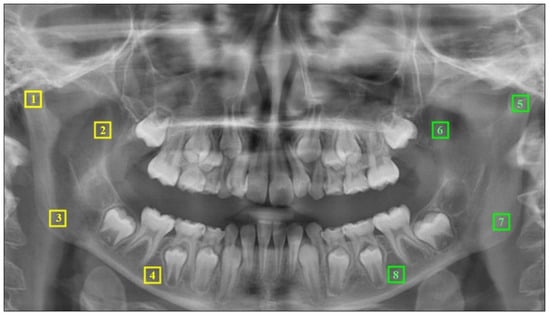

2.4. Fractal Analysis

3.1. Intra-Group and Inter-Group Comparison Results by Measurement Regions

3.1.1. For Mandibular Condyle

3.1.2. For Mandibular Angulus

3.1.3. For Mandibular Corpus

3.1.4. For Mandibular Coronoid